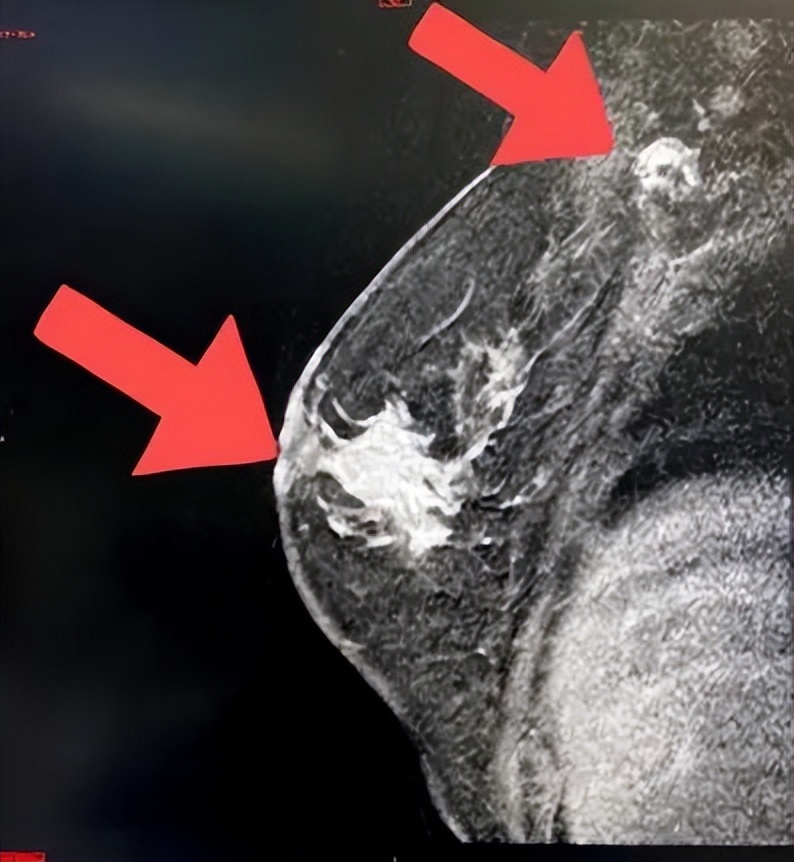

2021年11月29日乳腺MR提示:右侧乳腺异常信号肿物较前缩小,现约2.7*1.6cm,形态不规则,右腋窝淋巴结,较前略缩小,现短径约1.3cm,考虑转移。

2022年1月6日乳腺MR提示:右侧乳腺肿物较前缩小,边界欠清,短径1.1cm,右侧腋窝淋巴结短径约0.8cm。

2022年2月11日乳腺MR提示:右侧乳腺肿物较前进一步缩小,边界欠清,原肿物处现仅见点状强化灶,约0.4cm,右腋窝淋巴结现已不具体。

2021.9.30

2022.1.6

2022.2.11

图2 乳腺核磁

治疗6个周期后,2022.2.11乳腺MR显示靶病灶显著缩小,临床疗效评估为PR。